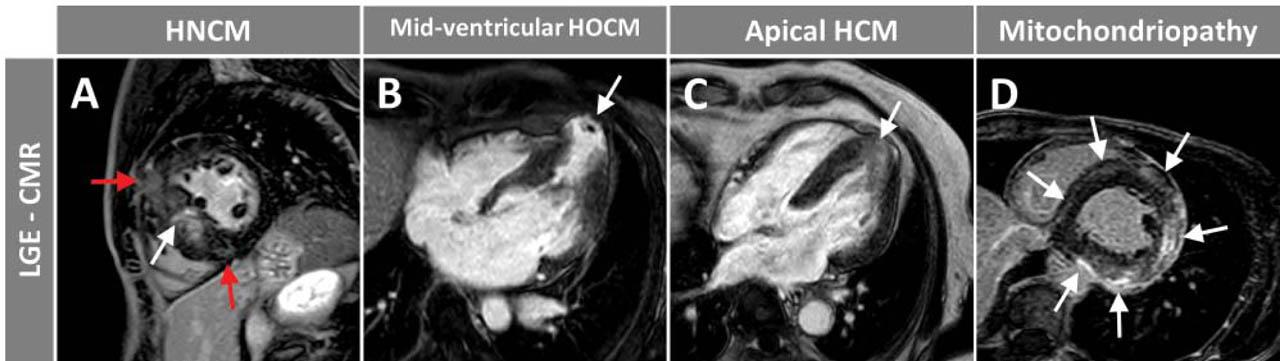

Figure 2

Exemplary LGE images in three patients with different forms of hypertrophic cardiomyopathy (HCM) (A, B, C) and in one patient with inherited primary mitochondrial disease (D). In the first case, with non-obstructive HCM (A), a typical, non-ischemic, patchy LGE in the hypertrophied septum (white arrow) together with focal LGE in the RV insertion points (red arrows) is present. In the second case, with mid-ventricular obstructive HCM (B), transmural LGE with apical aneurysm formation and small apical thrombus can be noticed (white arrow). In the third case, with apical HCM (C), diffuse, non-ischemic LGE in the hypertrophied apical segments can be depicted (white arrow). Lastly, in the mitochondriopathy patient (D), extensive, circular, subepicardial/intramural (non-ischemic) LGE (white arrows) and concentric LV hypertrophy are seen.